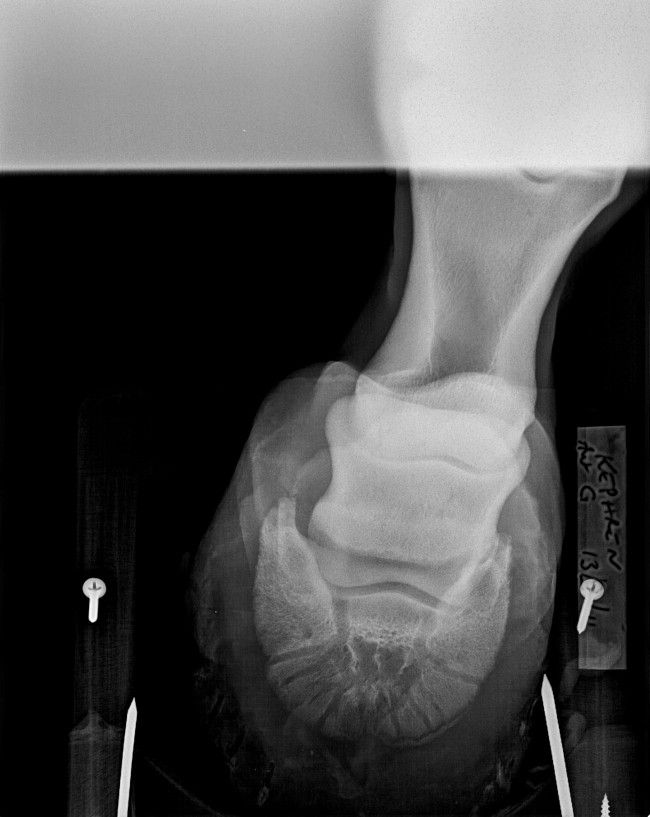

| Dire merci | Bonsoir, titre pas très explicite je vous l'accorde ! Je vais essayer de faire court. J'avais fais un post sur les souci de fourbure de Kephren (bascule P3 help). Mais je réexplique : PS de 10 ans arrivé fourbu il y a 3 ans et demi. Ferré avec toutes sortes de fers sans succès. Plusieurs tentatives pieds nus mais il souffrait trop. Finalement re déferré en juin 2013 car les fers ne tenaient plus que 3 jours, tout le pied était arraché par les déferrages intempestifs, et la résine lui provoquait une inflammation et une nouvelle crise. Bref, donc pieds nus depuis 8 mois, aidé de chaussons 24h/24 pendant 4 mois, puis étant dans la boue, sans rien. Visuellement il semble que nous ayons bien rattrapé la bascule de la phalange, Kephren marche à présent pieds nus, mais encore très sensible sur terrain irrégulier. Depuis environ 2 mois son antérieur gauche est chaud de temps en temps dans ces moments la, il n'est pas à l'aise. Avant hier je décide de refaire des radios pour voir ou on en est : Verdict du véto : la bascule est en bonne voie, bien rattrapée, mais la phalange est très abimée, nécrosée, elle est bouffée !!! Le véto a perdu les premières radios de 2011, donc ne peut pas comparer J'ai essayé de lui demander plus d'explications mais je n'ai pas pu en avoir ... Sachant qu'il y a 3 ans il m'a dit : c'est foutu y a rien à faire on peut pas rattraper la bascule... et sachant que finalement je suis en train de prouver le contraire, j'attends d'autres avis, j'ai moyennement confiance ... J'ai envoyé les radios par mail à la clinique véto de Gironde, on m'a répondu qu'on pouvait, à force de parage adapté, redresser un les aplombs et la phalange mais que ce sera long... merci mais c'est déjà ce qu'on fait depuis 8 mois, ça répond pas à ma question, la phalange est bouffée oui ou non ? Et si oui pourquoi et que peut on faire ?? toujours pas eu de réponse ![]() Qu'en pensez vous ?? Merci ! Voici les radios de 2011 : [url=https://www.1cheval.com/membre/services/photos/images/103924.jpg] ![]() [/url] [url=https://www.1cheval.com/membre/services/photos/images/103925.jpg] ![]() [/url] et voici celles d avant hier : [url=https://www.1cheval.com/membre/services/photos/images/175921.jpg] ![]() [/url] [url=https://www.1cheval.com/membre/services/photos/images/175922.jpg] ![]() [/url] |

DéconnectéDire merci | Sur la radio de 2011, on voit déjà que le bord solaire de P3 est irrégulier, voir possiblement fracturé sur le côté droit. Je ne vois pas de bascule plus que cela de P3. Dommage qu'il n'y ait pas de nouvelle vue récente du bord solaire. Sur les deux autres radiographies récente, on voit un remaniement osseux de la pinte de P3 et ce qui pourrait être une plus forte perte osseuse du bord solaire que sur les radios de 2011 – mais il faudrait une vue "bord solaire" récente pour confirmer ou infirmer. Mais surtout, ce qui me saute aux yeux sur la radios récentes, c'est 1/ P2 parallèle au sol (ce qui contribue à endommager encore plus P3 2/ le mauvais alignement des phalanges (alors qu'il était quasi correct en 2011), avec un axe pied-pâturon brisé vers l'arrière. |

DéconnectéDire merci | En premier lieu, et avec mes excuses, c'est P3 parallèle au sol que je voulais écrire. Oui, les phalanges étaient mieux alignées en 2011. Peut-être que le cheval marche mieux et que son sabot ressemble à quelque chose (photo ?), mais une chose est indéniable, P3 s'est détériorée depuis 2011. |